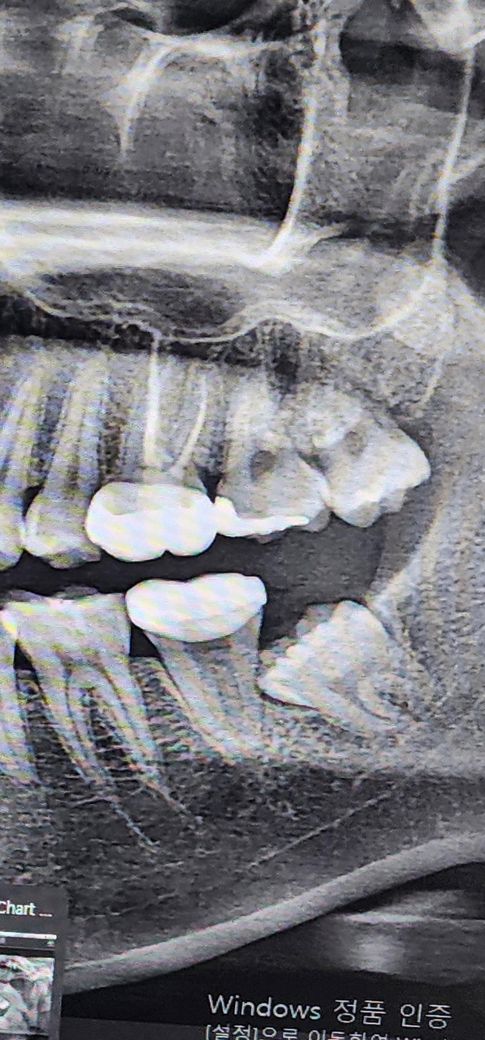

아래에 난 사랑니 두개가 있는데 이거 어떻게 해야할까요

저 사랑니들 꼭 뽑아야 하는 사랑니인가요?

사랑니가 경사져 매복되어 있어 그대로 두면 바로옆 어금니가 상하게 되니 가능한 빨리 뽑는 것이 좋습니다. 구강외과 전문의가 진료하는 동네치과 가도 됩니다. 이런 케이스의 경우 사랑니 뽑은 후 후유증 나타날 확률은 비행기 사고날 확률 보다 조금 높은 정도로 보면 됩니다.

지금 문제가 없다면 무조건 뽑아야하는 것은 아니지만 맹출 방향을 봤을때는 아무래도 뽑아주는게 좋긴 합니다. 신경관이 근처에 있어보이긴 하지만 CT를 찍어봐야 알 수 있고 저정도라면 치과마다 다르긴 해도 대부분 발치할 수 있습니다. 구강외과 전문의 선생님이 있는 곳은 다 발치해주실겁니다.

발치과정에서 신경이 손상될 가능성은 매우 낮긴 하고 보통 임플란트 시에 사고가 나는 것 처럼 신경 자체를 절단하거나 손상시키는 것이 아니라 대부분 신경이 눌려서 일시적으로 그러는 경우가 많아 보통 6개월에서 1년 이내에는 대부분이 회복 되고 간혹 후유증이 남는 분들의 경우에는 혀나 입술 볼쪽 감각 저하와 감각이상 반응을 나타냅니다.

저 사랑니들 꼭 뽑아야 하는 사랑니인가요? -> 옆 어금니의 뿌리를 흡수시킬 가능성 있습니다.

신경 잘못 건드려서 사고 날 확률 얼마나 돠나요? -> 일시적, 반영구적 신경손상 등인데 가능성 낮습니다

발치 시기는 정해져있진 않으나 나이가 들수록 뼈와 유착되어 사랑니 빼기는 어려워집니다.